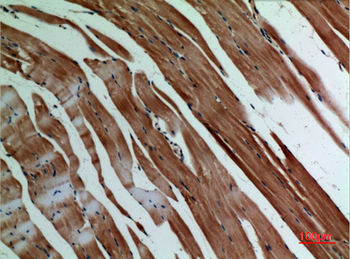

α-SMA Polyclonal Antibody

Catalog Number: orb1411650

| Catalog Number | orb1411650 |

|---|---|

| Category | Antibodies |

| Description | Rabbit polyclonal antibody to α-SMA. |

| Clonality | Polyclonal |

| Species/Host | Rabbit |

| Conjugation | Unconjugated |

| Reactivity | Human, Mouse, Rat |

| UniProt ID | P68133 |

| Tested applications | IHC-P, WB |

| Dilution range | WB: Western Blot: 1/500 - 1/2000. IHC-p: 1:100-300 ELISA: 1/20000. Not yet tested in other applications. |

| Storage | Maintain refrigerated at 2-8°C for up to 2 weeks. For long term storage store at -20°C in small aliquots to prevent freeze-thaw cycles |

| Alternative names | ACTA1; ACTA; Actin, alpha skeletal muscle; Alpha-a Read more... |

| Note | For research use only |